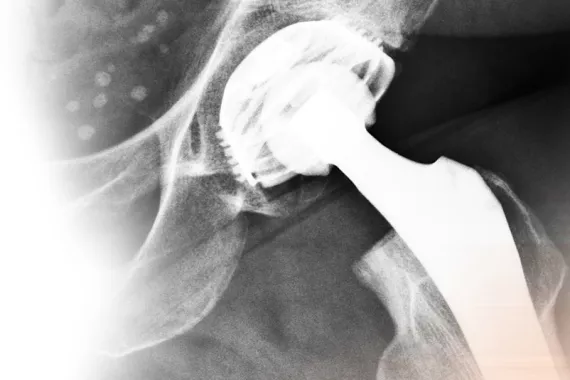

Metal-on-metal hip devices were originally thought to be a more durable alternative to ceramic or plastic models, but some studies have shown that they may deteriorate faster, expose patients to high levels of metals such as cobalt and chromium, and fail at a higher rate than older implants.

In fact, approximately one in 12 recipients of metal-on-metal devices may require corrective surgery within five years of implantation.